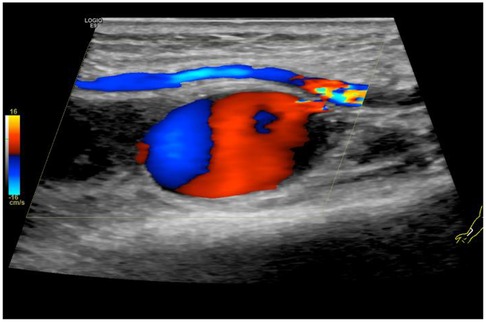

A 65-year-old Chinese male with a medical history of hypertension, dyslipidemia, and coronary artery disease was admitted due to unstable angina. Coronary angiography performed via right transradial access revealed significant triple-vessel disease, and PCI with drug-eluting stent implantation was successfully conducted. The procedure was uncomplicated, and hemostasis was achieved using a TR compression band device. On postoperative day 2, the patient reported swelling and tenderness at the right wrist. Physical examination identified a 2.5 × 2 cm pulsatile, tender mass with an audible bruit. Doppler ultrasonography confirmed the diagnosis of radial artery pseudoaneurysm, characterized by a narrow neck (2 mm) and a classic yin-yang flow pattern (Figure 1). After obtaining informed consent, UGTI was performed under continuous ultrasound guidance. A 21-gauge needle was used to inject 1.5 mL of purified human thrombin (500 IU/mL) into the pseudoaneurysm sac. Complete thrombosis occurred within 30 s (Figure 2). Post-procedurally, the mass became non-pulsatile, and follow-up ultrasound at 24 h confirmed sustained occlusion without recurrence (Figure 3). The patient remained asymptomatic and free of neurological or vascular complications.

Figure 1

Color Doppler ultrasound image showing blood flow dynamics. Red indicates flow toward the probe, blue shows flow away. A central structure, likely a blood vessel, displays these color variations against a gray background.

Figure 1. Doppler ultrasound of the right wrist was carried out, which confirmed the diagnosis of pseudoaneurysm of radial artery.